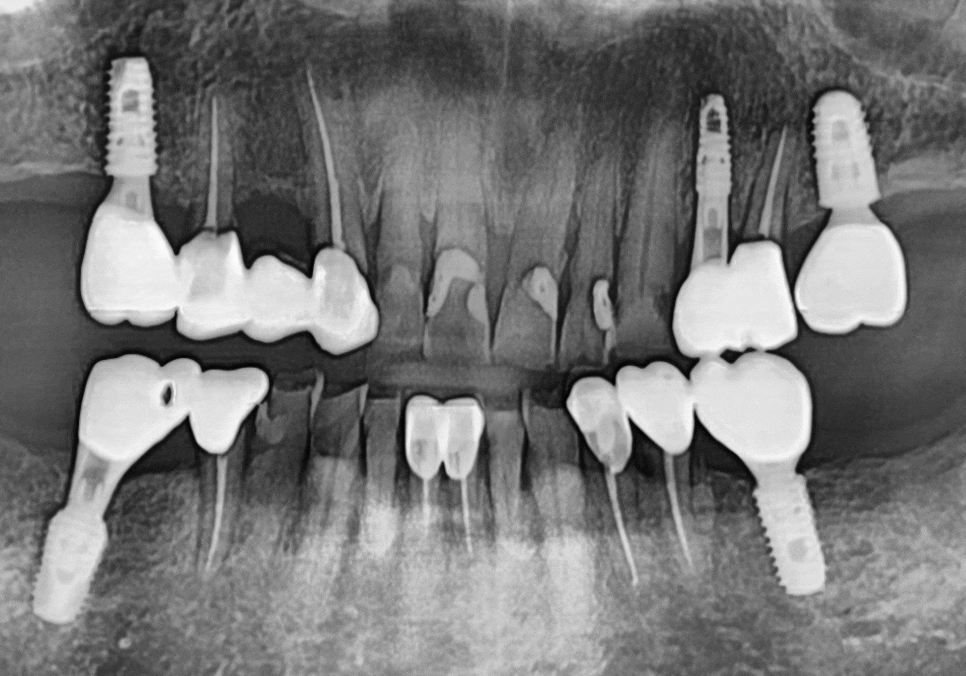

이번에 문제가 생긴 앞니들은

신경치료 후 보철물을 연결하는

스플린트 형태로 제작하기로 계획했습니다.

#12~23 신경치료 및 지르코니아 스플린트

#42, 43, 44 및 #32, 33 신경치료

및 지르코니아 스플린트

3)진행 방식

연세를 고려하여 상악부터 순차적으로 천천히 진행